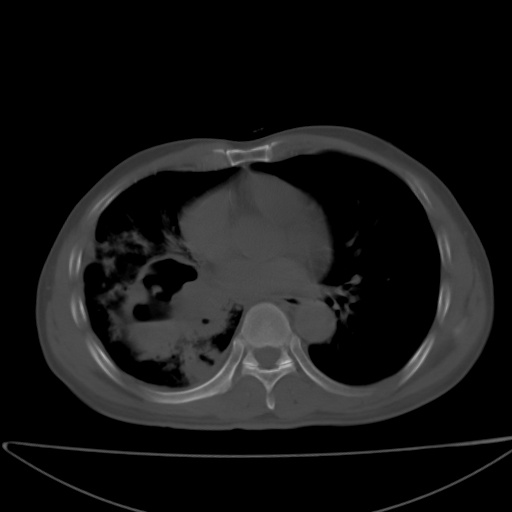

以下是引用jsgdoctor在2008-11-6 22:12:00的发言:[br]右主支气管壁明显增厚,管腔狭窄.考虑为右侧中央型肺癌伴阻塞性炎症\\肺脓肿.

以下是引用zjzjr在2008-11-6 20:25:00的发言:[br]中心型肺ca,合并阻塞性肺炎

以下是引用zsl6918在2008-11-6 19:43:00的发言:[br]右侧中心性肺癌(鳞癌)